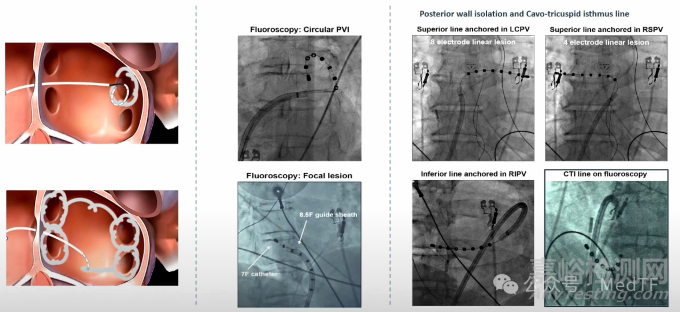

ArgáMedtech在HRS2025會議上公布其特有的正弦波的PFA技術---Sine-Burst Electroporation (CSE) System的臨床研究數據(BURST-AF),并發表在《 Heart Rhythm Journal》。研究顯示:CSE消融實現了肺靜脈、后壁及CTI的持久隔離,并發癥發生率低。

CSE是一款獨特的PFA消融技術,其采用Argó Medtech獨有的正弦波,而非傳統PFA技術的方波。因此CSE也被Argó Medtech譽為下一代PFA技術。

CSE除了在PFA能量上進行創新外,在消融導管上也進行革新。CSE的消融導管是一根多用途的消融導管。CSE的消融導管可以成形為產生環形、線性和局灶性消融損傷。

由于CSE的消融導管多用途特性,簡化了手術過程,減少術中消融導管更換,降低了在移除一根導管和重新插入另一根導管時引入氣泡的風險,并降低了成本。